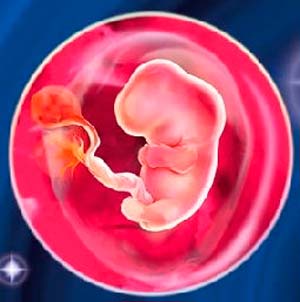

What does the future baby look like?

The largest parts of the body are the head and torso. The arms and legs are tiny processes with tubercles-fingers. The size of the fetus (more precisely, the embryo) in the 6th obstetric week reaches 4 mm, weight - up to 2 g. And here is how it develops:

And here is a new miracle - the placenta is developing, the umbilical cord is forming. The baby is no longer pressed close to the wall of the fetal egg. He swims freely in the amniotic fluid and makes his first movements. But mother will not be able to feel it very soon. But she feels a lot more.